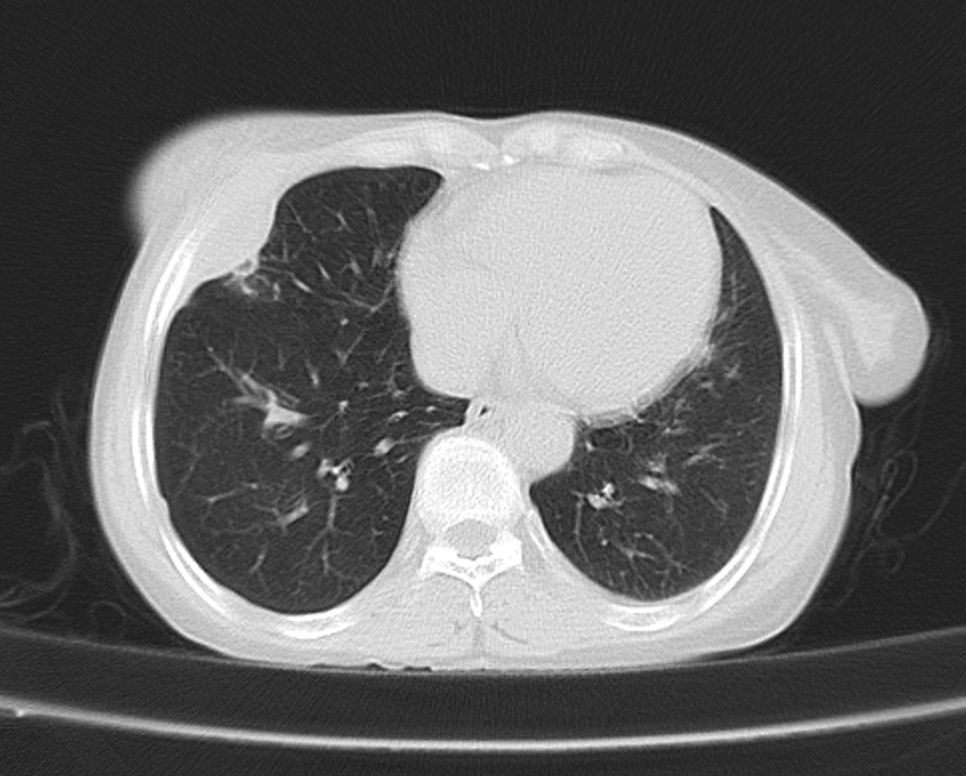

标题: CT21609:右乳包块1年,请各位讨论分析一下,乳腺CA, [打印本页]

标题: CT21609:右乳包块1年,请各位讨论分析一下,乳腺CA,

考虑---右乳癌并胸壁、肋骨、双肺转移。

考虑乳腺癌侵犯肋骨、胸壁及两肺转移可能性大。

右乳癌并胸壁、肋骨、双肺转移。

考虑右侧乳腺癌侵犯肋骨、胸壁及两肺转移。

支持考虑---右乳癌并胸壁、肋骨、双肺转移。

考虑右侧乳腺癌侵犯肋骨、胸壁及两肺转移可能。

考虑右侧乳癌并胸壁、肋骨及双肺多发性转移。